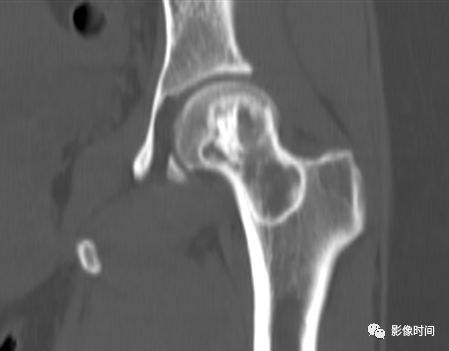

四、肿瘤内液-液平面

肿瘤内液-液平面多数是病灶内囊变出血所致,MRI T2W1 为上部呈高信号下部呈中低信号的液-液平面。CT 可为上部低密度下部高密度的液-液平面(图 32)。液-液平面常见于动脉瘤样骨囊肿、但也可见于骨内腱鞘囊肿(图 33)、囊性血管瘤病等其他肿瘤和肿瘤样病变。

图 32 肿瘤内液-液平面:动脉瘤样骨囊肿

图 33  肿瘤内液-液平面:动脉瘤样骨囊肿